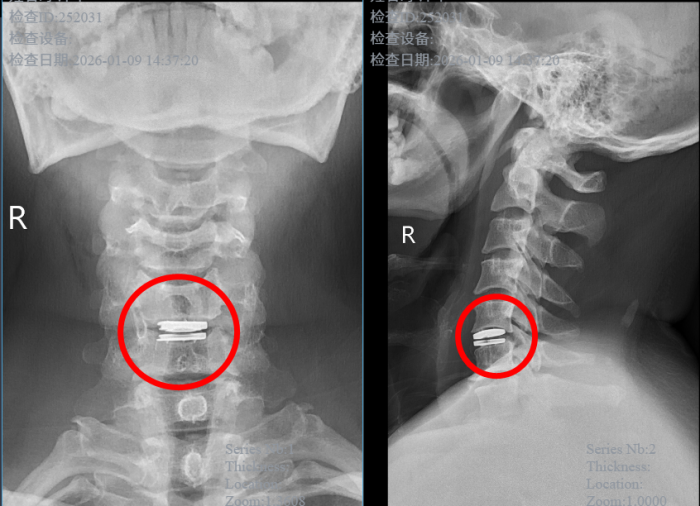

手术当天,脊柱外科唐光副主任医师在高清显微镜的精准引导下,通过一个微创小切口,精准摘除病变椎间盘,植入适配的人工椎间盘假体,完美恢复颈椎正常生理曲度和椎间高度。整个手术出血量极少,神经保护精准到位,真正实现了 “微创、精准、安全” 的治疗目标。

术后恢复速度远超李先生预期:术后第 1天,颈肩疼痛和双上肢麻木症状就明显缓解,能够自主翻身、坐起;术后第2天,在医生指导下顺利下床行走,颈部活动灵活无受限,经影像学检查确认人工椎间盘位置精准、稳定性良好;术后第5天,李先生各项指标均达到出院标准,带着满意的笑容顺利出院。“原以为颈椎手术要躺很久,没想到这么快就能正常活动,医生技术太厉害了!”出院时,李先生带着家属,向脊柱外科团队表达了由衷的感谢。